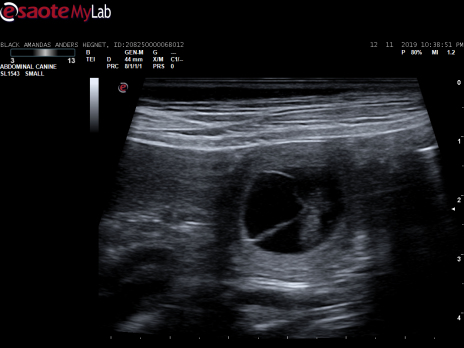

Scanningsbilleder fra den 12. november 2019

Black amandas Signed With Passioner i dag blevet scannet på Hinnerup Dyreklinik. Scanningen viste, at hun er meget drægtig.

Vi så mange fine små bobler, med hvert sit lille bankende hjerte

Herlighederne kommer til verden ca. den 20. december 2019.